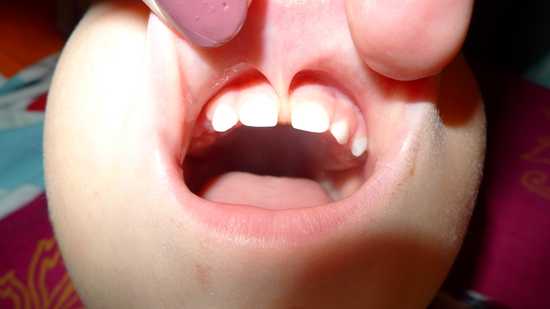

Диагностировать проблему очень просто, нужно лишь приподнять губу, оценить положение полости. Если слизистая складка начинается в середине губы , на 4-6 мм выше десны, ее можно назвать слишком короткой. Такая уздечка может стать причиной развития патологий.

Нормальной считается уздечка, которая вплетается в десну на 0,5-1 см от основания передних резцов. Более низкое ее расположение приводит к тому, что уздечка может заходить за передние резцы, а место ее крепления с десной вообще не просматривается. То есть уздечка начинается в середине верхней губы и крепиться примерно на 0,4-0,6 см выше десны, обосновываясь в щели между передними резцами.

Короткую уздечку очень легко увидеть при визуальном осмотре. Для этого верхнюю или нижнюю губу отводят в сторону и рассматривают. При нормальном расположении она не влияет на прикус и не мешает разговаривать. Низкое же ее расположение может привести к множественным нарушениям не только речи, но и эстетики лица. Чтобы не допустить дефектов губы и речи ребенка, проводят операцию по пластике уздечки.